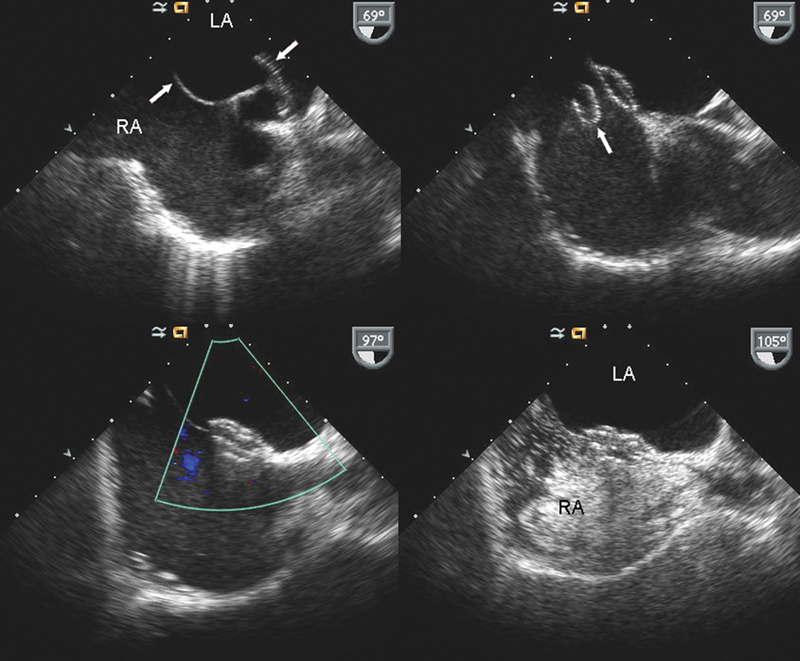

فحوصات تشخيصية لبعض امراض القلب والشرايين التاجية